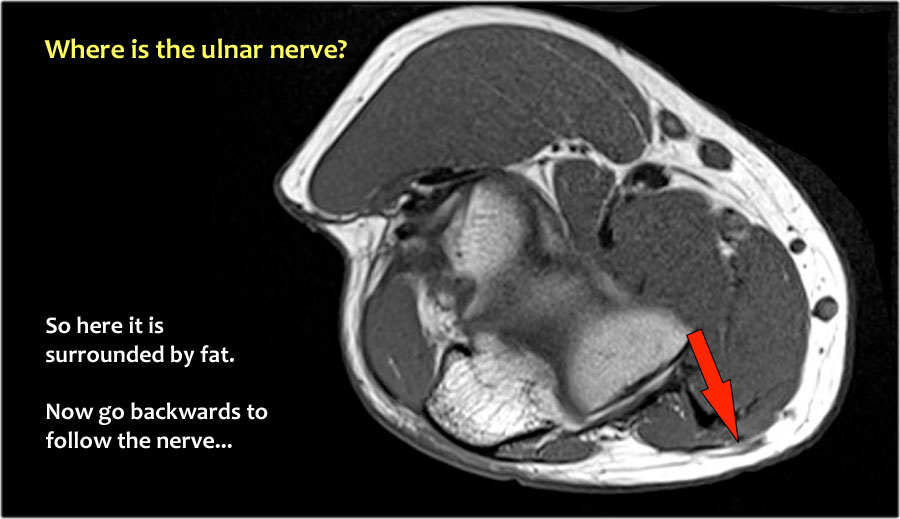

Một cách để thực hiện là đi theo các cấu trúc về phía xa cho đến khi tìm thấy dây thần kinh trụ ở phía xa tại vị trí bình thường của nó ở vùng cẳng tay gần được bao quanh bởi mô mỡ.

Sau đó khi bạn theo dõi nó về phía gần, bạn sẽ nhận thấy rằng đây là một trường hợp chuyển vị dưới da.